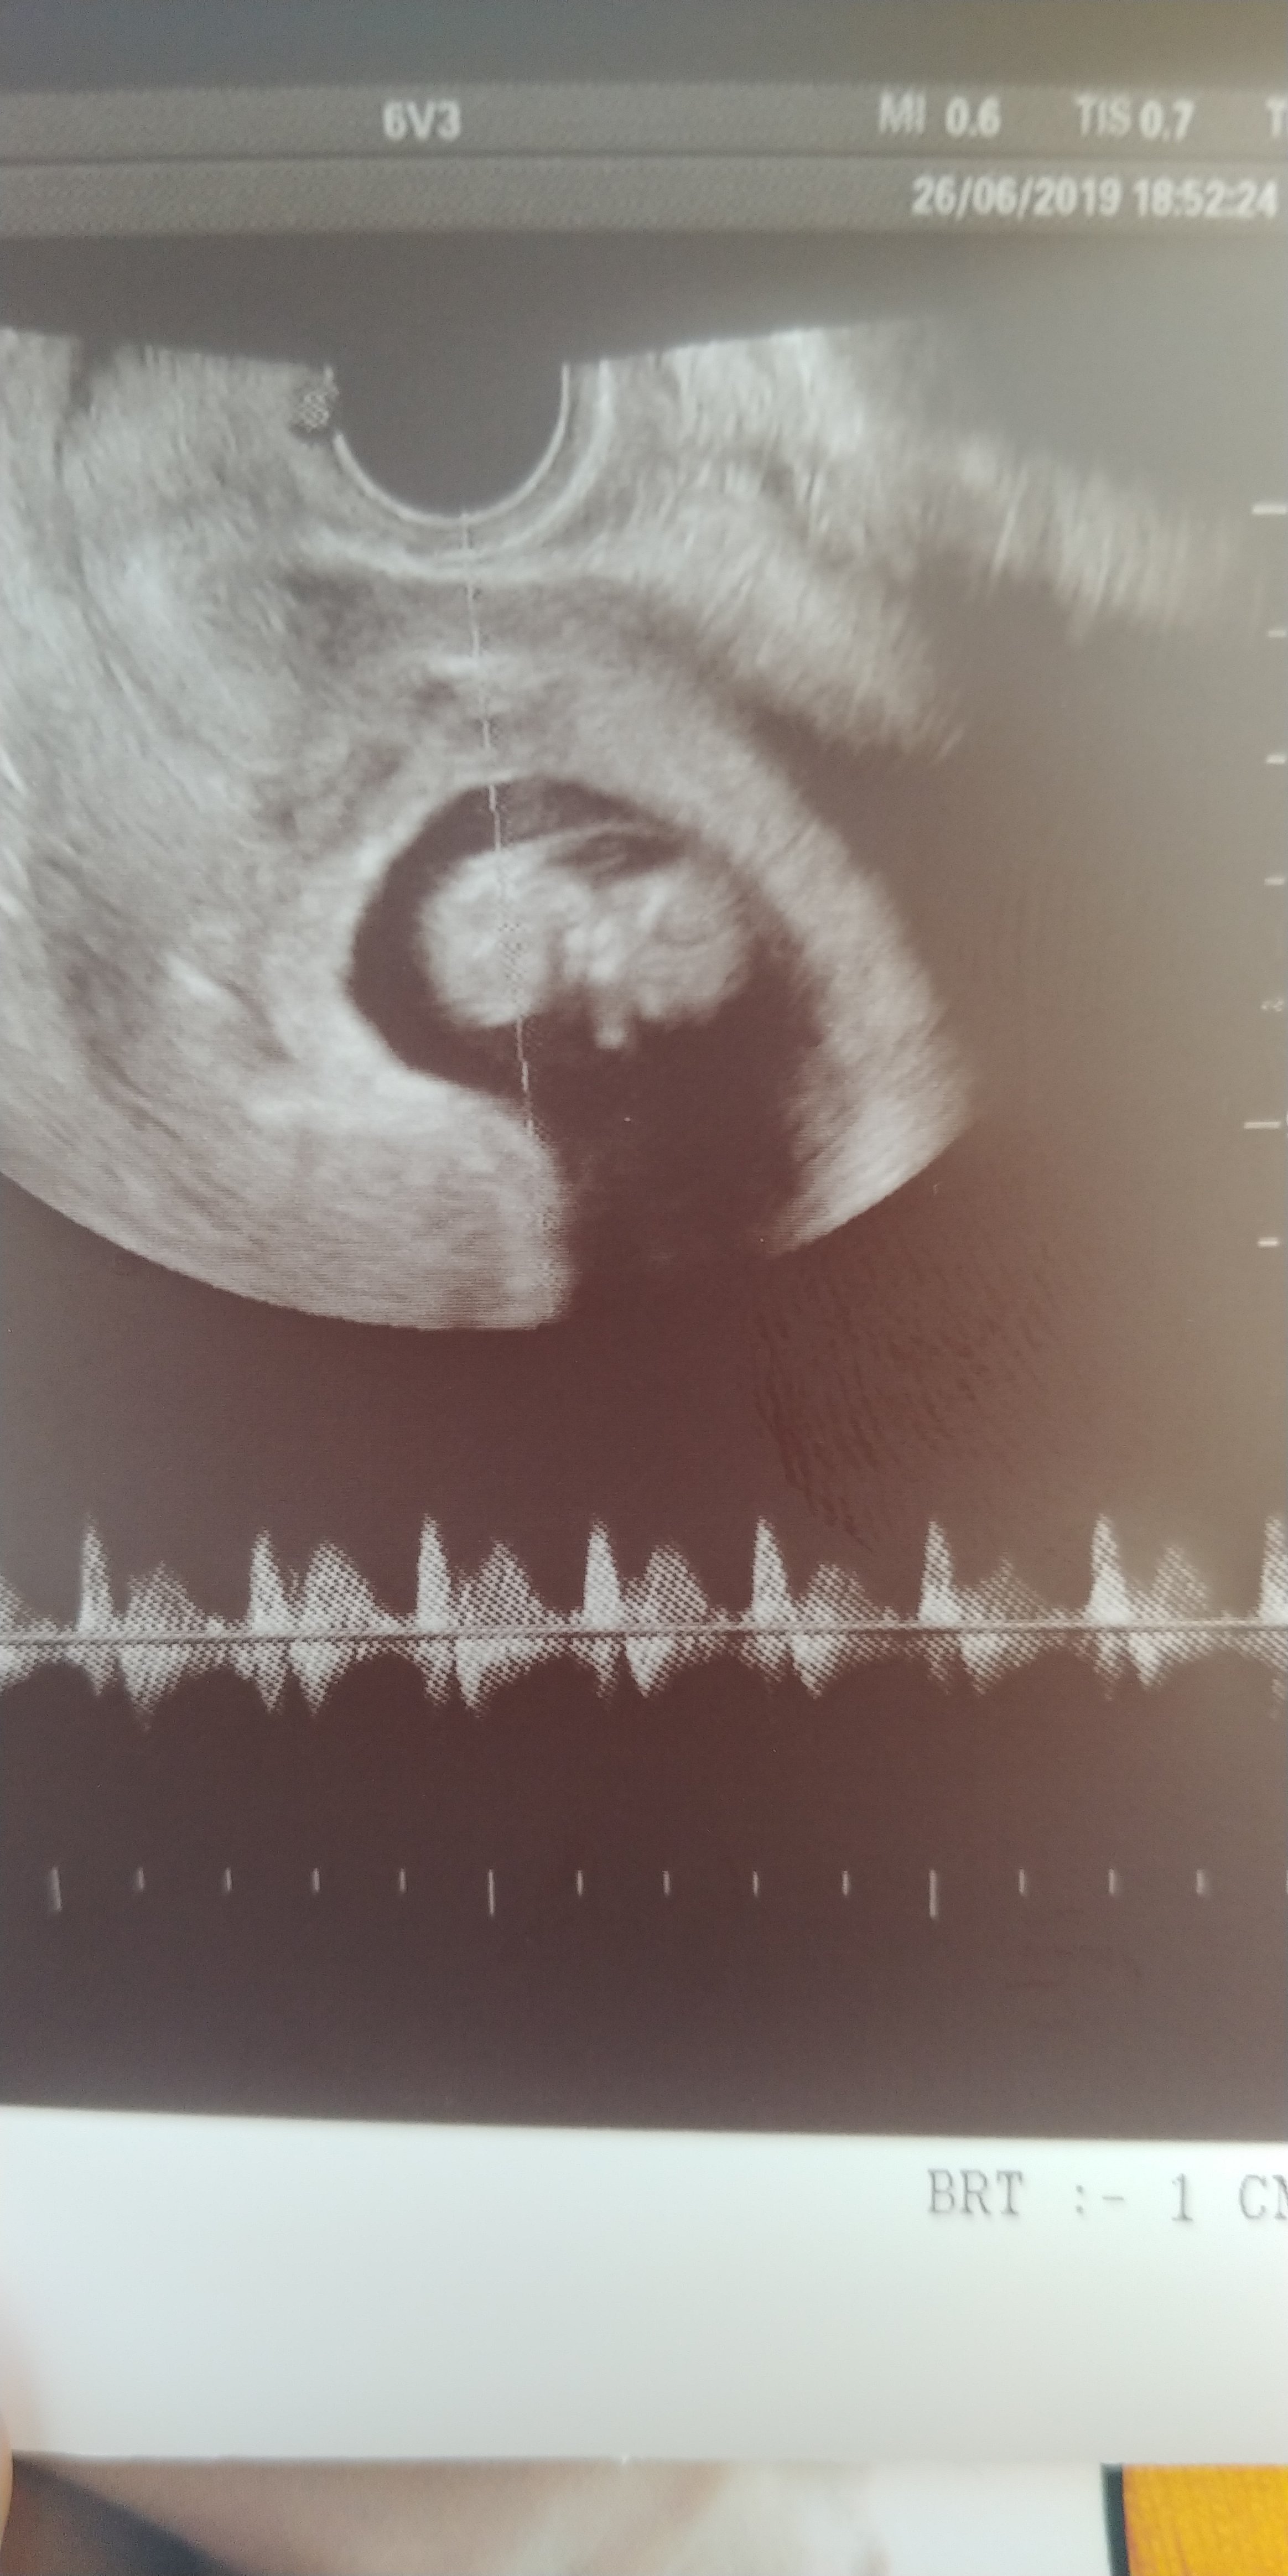

Hej kochana dziekujemy rośniemy , mały/mała już 3 cm, pieknie rusza rączkami...plakalam na USG ostatnim.Hej kochana co u ciebie mam nadzieję że wszystko ok. Tak odpoczywam i myślę o tobie czy ładnie rosniecie.

załączam zdjęcie.

Hej kochana dziekujemy rośniemy , mały/mała już 3 cm, pieknie rusza rączkami...plakalam na USG ostatnim.

12 tydzien zaraz się kończy

12 tydzien zaraz się kończy![]()